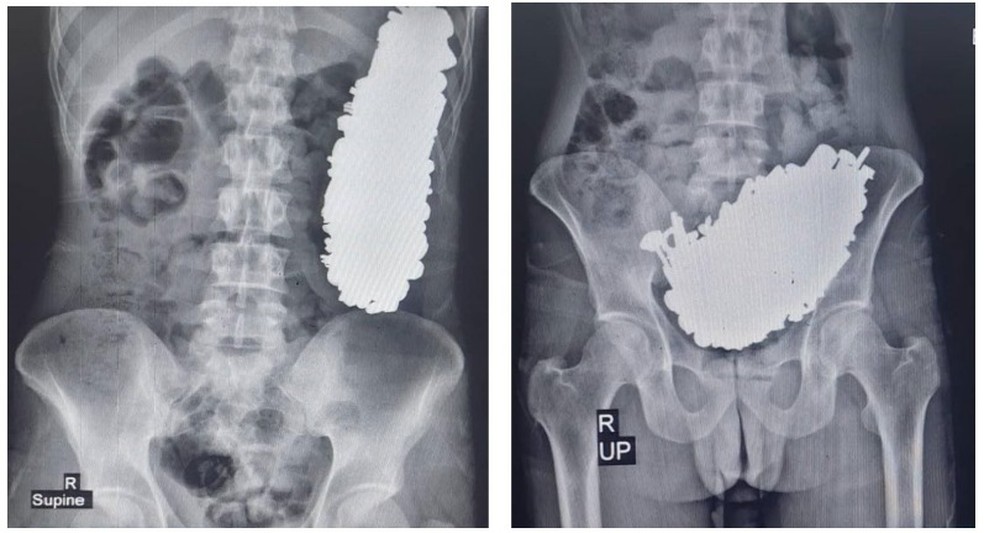

Os acompanhantes dele mencionaram um histórico de ingestão de peças metálicas três meses antes da ida até à unidade de saúde. Os médicos solicitaram exames de radiografia e endoscopia e encontraram múltiplos objetos metálicos que causaram obstrução gástrica no paciente. Ainda assim, ele apresentava sinais vitais estáveis e estava consciente. Ao todo, foram achados 452 parafusos, porcas, chaves, pedras e outras partes metálicas, pesando 2,9 quilos.